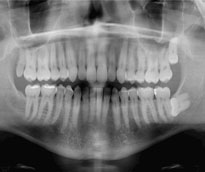

Oral Diagnosis and Radiological